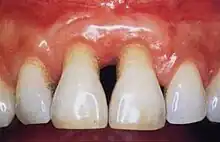

Gingivitis is a common condition that affects the gingiva or mucosal tissues that surround the teeth. The condition is a form of periodontal disease; however, it is the least devastating, in that it does not involve irreversible damage or changes to the periodontium (gingiva, periodontal ligament, cementum or alveolar bone). It is commonly detected by patients when gingival bleeding occurs spontaneously during brushing or eating. It is also characterized by generalized inflammation, swelling, and redness of the mucosal tissues. Gingivitis is typically painless and is most commonly a result of plaque biofilm accumulation, in association with reduced or poor oral hygiene. Other factors may increase a person's risk of gingivitis, including but not limited to systemic conditions such as uncontrolled diabetes mellitus and some medications. The signs and symptoms of gingivitis can be reversed through improved oral hygiene measures and increased plaque disruption. If left untreated, gingivitis has the potential to progress to periodontitis and other related diseases that are more detrimental to periodontal and general health.[10]

Healthy gingiva can be described as stippled, pale or coral pink in Caucasian people, with various degrees of pigmentation in other races. The gingival margin is located at the cemento-enamel junction without the presence of pathology. The gingival pocket between the tooth and the gingival should be no deeper than 1–3mm to be considered healthy. There is also the absence of bleeding on gentle probing.[11]

Signs and symptoms of periodontal disease: bleeding gums, gingival recession, halitosis (bad breath), mobile teeth, ill-fitting dentures and buildup of plaque and calculus.[16]